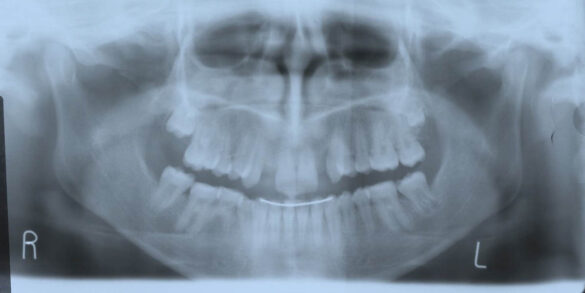

La momentul prezentării în clinică, în decembrie 2002, pacienta avea 8 ani şi o lună şi suferea de fibroză chistică şi de o deficienţă de dezvoltare a etajului mijlociu al feţei. Aceasta prezenta o anomalie de clasa I care mima o anomalie de clasa a III-a. Incisivii centrali, laterali şi caninii temporari maxilari, precum şi molarii prim şi secund de pe partea stângă erau în ocluzie inversă. În plus, pacienta prezenta coloraţii ale dinţilor de etiologie idiopatică (fig. 1). Autorii au considerat coloraţiile ca fiind de suprafaţă, extrinsece şi nu determinate de fibroza chistică, dovadă îndepărtarea acestora prin periaj profesional. Radiografia panoramică efectuată cu 6 luni înainte de prezentarea în clinica stomatologică relevă anodonţia incisivilor laterali superiori şi a premolarului secund drept inferior, ca şi posibila incluzie a caninilor maxilari, în special a celui stâng (fig. 2).

A doua etapă a tratamentului a fost amânată până în aprilie 2006, când pacienta a împlinit vârsta de 11 ani şi 5 luni. În acel moment, fetiţa prezenta erupţie şi dezvoltare radiculară adecvată, astfel că aparatele fixe aplicate acum n-ar fi purtate o perioadă îndelungată. Ocluzia inversă frontală şi angrenajul invers lateral fuseseră corectate; totuşi, exista o diastemă mare, în principal cauzată de lipsa incisivilor laterali superiori (fig.3). În acest moment, radiografia panoramică relevă anodonţia incisivilor laterali maxilari şi a premolarului secund drept mandibular, o anatomie redusă a rădăcinilor incisivilor centrali superiori, incluzia caninului superior stâng şi dezvoltarea întârziată a rădăcinii celui de-al doilea premolar inferior (fig. 4).

În aprilie 2009, după 37 luni de tratament, au fost îndepărtate aparatele fixe (fig. 6). Pentru contenţie, s-a aplicat un retainer fix colat pe faţa linguală a celor şase dinţi frontali inferiori şi o placă palatinală Hawley care încorporează dinţi acrilici în dreptul incisivilor laterali pentru a menţine un aspect estetic până când medicul protetician va putea realiza punţile dentare. În plus, s-a utilizat un arc vestibular care să consolideze contenţia şi care să permită aplicarea unor forţe uşoare, cu direcţie linguală, dacă este necesar.25 Croşetele ”în deget” sunt situate distal de incisivii centrali maxilari şi mezial de caninii superiori, pentru a permite o deplasare discretă mezio-distală a dinţilor, dacă este necesar (fig. 7).Înainte de îndepărtarea aparatului, a fost consultat medicul protetician. S-a pus problema dacă pacienta ar avea dificultatea de a purta pe termen lung un aparat mobil de contenţie, din cauza dificultăţilor de respiraţie şi a tusei, asociate cu fibroza chistică. În plus, din cauza anodonţiei de incisivi laterali superiori, osul alveolar este dezvoltat insuficient şi prezintă, astfel, dimensiuni prea reduse pentru inserarea implantelor dentare; procedura de augmentare a ţesuturilor moi şi dure ale crestei alveolare ar fi inevitabilă. Vârsta pacientei şi creşterea şi dezvoltarea corespunzătoare au fost, de asemenea, luate în considerare.19 Ortopantomograma finală relevă anodonţia molarilor de minte inferiori şi a celui superior drept pe lângă anodonţia incisivilor laterali maxilari şi a premolarului secund drept inferior. De asemenea, se remarcă aplatizarea rădăcinilor incisivilor centrali maxilari, care era prezentă şi pe radiografia efectuată înainte de tratament (fig.8).